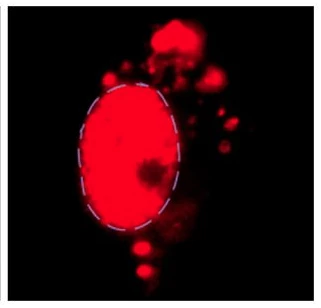

After years of research, the research group of the Institute of Biological and Chemical Interdisciplinary Research, Shanghai Institute of Organic Chemistry, Chinese Academy of Sciences found that RIPK1 activation can be used in mouse models of neurodegenerative diseases and in human Alzheimer's disease and lateral sclerosis disease samples. detected. At the same time, inhibition of RIPK1 activity can attenuate inflammation and neuronal cell death in a mouse model of neurodegenerative diseases.

The team found an important role for the key regulatory factor RIPK1 in the cell death signaling pathway in neurodegenerative diseases. RIPK1 is a member of the "receptor-acting protein kinase" family and is responsible for the initiation and regulation of important physiological processes such as apoptosis, cell necrosis and cellular inflammation.